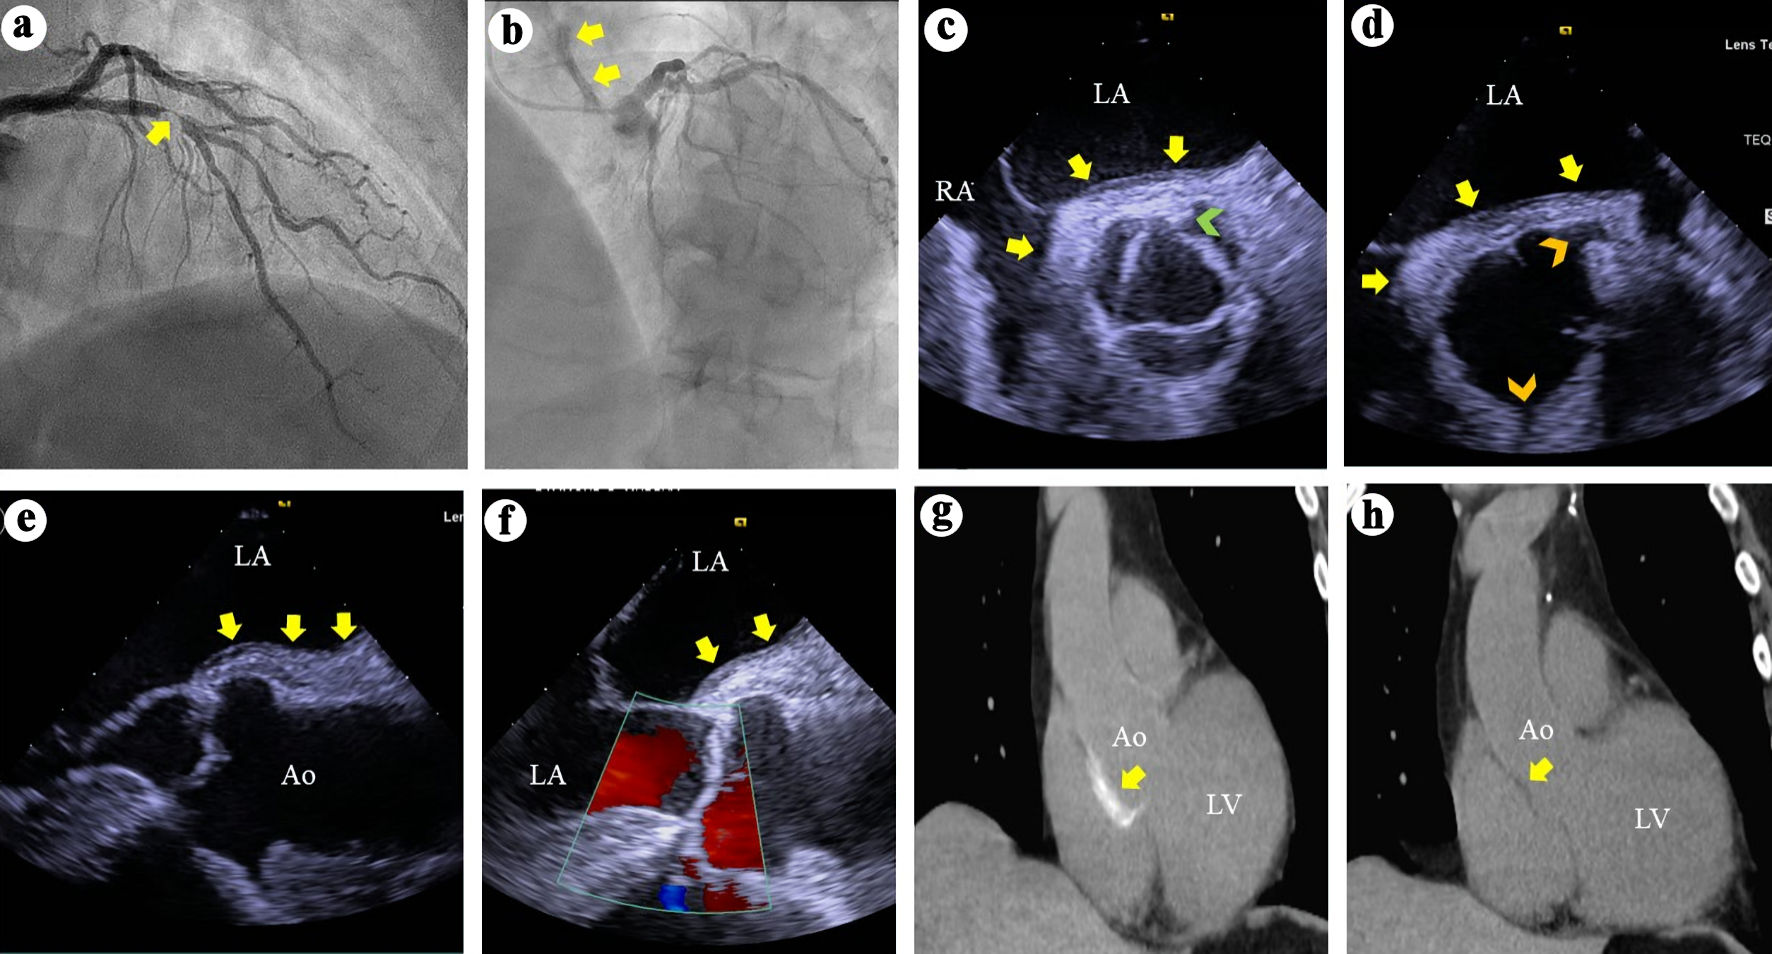

Figure 1. (a) Right anterior oblique view of the left coronary arteries angiography demonstrates a > 95% complex stenosis (arrow) of the left anterior descending coronary artery. (b) Left anterior and cranial view of the left coronary system demonstrates contrast hang-up or staining (arrows) on the aortic root and ascending aorta. (c) TEE short axis views at the aortic valve level during systole demonstrates soft tissue echo-reflectant thickening of the aortic root posterior wall with medial and lateral extensions (arrows) and a possible small intimal tear (green arrowhead). (d) TEE short-axis view of the aortic root during diastole demonstrates aortic wall thickening (arrows) and intact ostial left main and right coronary arteries (top and bottom arrowheads, respectively). (e, f) TEE long-axis views demonstrate soft tissue thickening of the posterior aortic root and ascending aortic wall (arrows) and intact aortic valve with no regurgitation. (g) Thoracic CT demonstrates contrast uptake at the aortic root and part of the ascending aorta (arrow). (h) Repeat thoracic CT 7 weeks later demonstrates resolution of the contrast uptake at the aortic root and ascending aorta. TEE: transesophageal echocardiography; CT: computed tomography; LA: left atrium; RA: right atrium; Ao: aorta; LV: left ventricle.

TEE showed soft tissue echo-reflectant thickening of the posterolateral aortic root at the level of the non-coronary and left coronary sinuses, with extension of less than 4 cm into the ascending aorta (Fig. 1c-f). A small intimal tear was suspected but not confirmed (Fig. 1c). No dissections involving the left main, LAD, or RCA were identified, and there was no aortic regurgitation (Fig. 1d, e).

Subsequently, a computed tomography angiogram (CTA) confirmed a small intramural hematoma primarily involving the posterior aortic root, extending less than 4 cm into the ascending aorta (Fig. 1g). Immediate surgical consultation was obtained.

Postoperatively, he had an uneventful recovery and was discharged on day 6 in stable condition with guideline-directed medical therapy, including dual antiplatelet therapy (aspirin and clopidogrel). He remained well on outpatient follow-up at weeks 2 and 6. A repeat CTA at week 7 demonstrated resolution of the intramural hematoma (Fig. 1h). He has experienced no recurrent events and remains clinically stable 4 years after presentation.